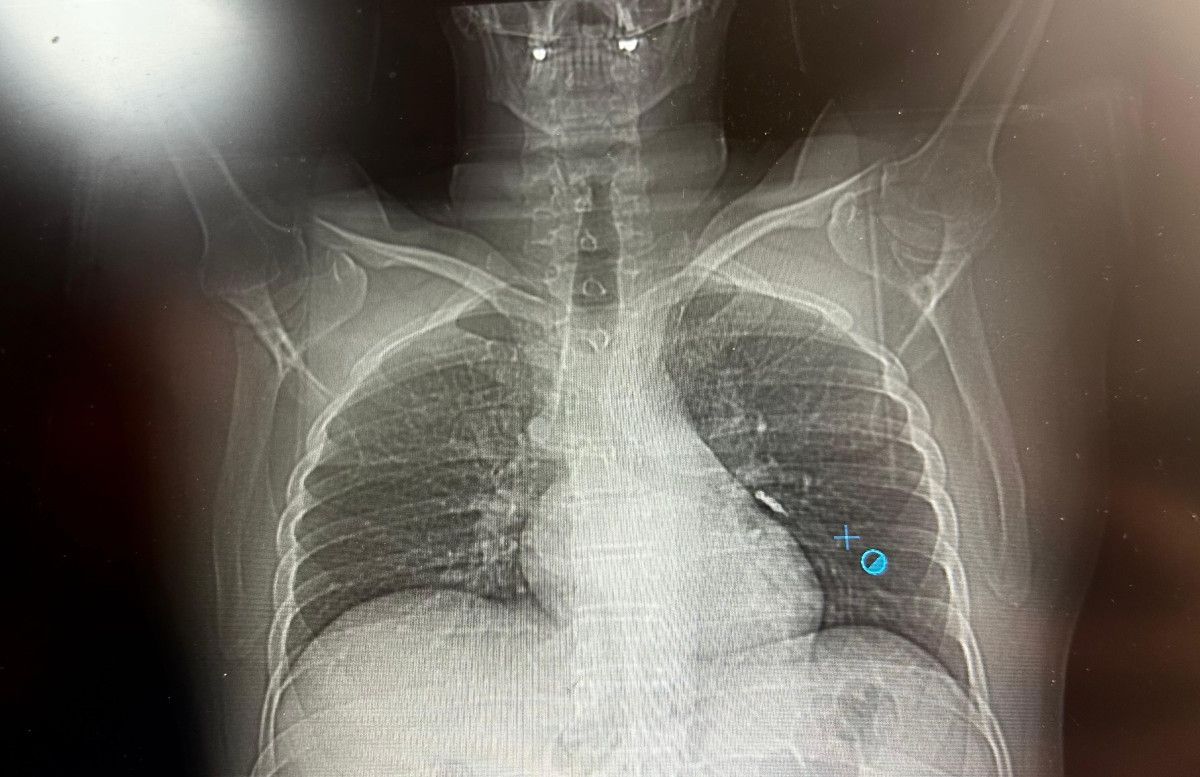

İlk olarak hastanenin ek hizmet binasında çekilen tomografi sonucunda, vidanın sol akciğerin hava yollarının yaklaşık dördüncü koluna kadar ilerlediği tespit edildiğini tabir eden Op. Dr. Aksoy, şunları kaydetti:

SOL AKCİĞERİN ÜST LOBUNA SAPLANDIĞI TESPİT EDİLDİ

Sol akciğerin üst lobunda saplanmış biçimde tespit edilen vida, vidalı yapısı ve bulunduğu pozisyon nedeniyle zahmetle yerinden oynatılabildi.